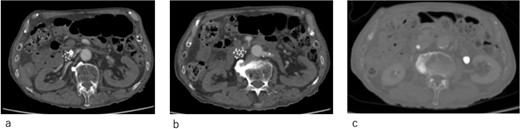

After confirming the absence of progressive anemia because of the hemorrhage from the femoral fracture, heparin was administered systemically. Following improved arterial blood oxygenation, NPPV was discontinued on hospital Day 3, and oxygen administration was discontinued on hospital Day 10. The patient was discharged on Day 15 of hospitalization. Enhanced computed tomography revealed that the IVCF did not move (Fig. 4a–c) and the pulmonary embolism improved; however, the thrombus remained in the left femoral and popliteal veins.

Computed tomography images 14 days after surgery. (a,b) The IVCF is still folded and not open. (c) Legs of IVCF are still folded.

IVCF is generally considered safe, with a low incidence of acute complications. In addition, instances of IVCF opening failure are very rare. Ganesh et al. reported that IVCF ‘failed to open’ only in 27 (0.18%) out of 14 784 cases [2]. The etiology of IVCF opening failure has been attributed to entanglement of the IVCF legs [3], misplacement into the gonadal or femoral veins [3, 4], or thrombus formation in the delivery sheath during deployment [5, 6]. In our case, the etiology was assumed to be entanglement of the IVCF legs or misplacement of the IVCF tip into the left gonadal vein based on the shape of the failed ICVF (Figs 2a and 4c).

Despite being effective in avoiding the migration of the unopened IVCF and treatment of the acute pulmonary thromboembolism, our approach remained of concern. IVCFs have been reported to cause chronic perforation to the IVC wall, even with appropriate deployment [9]. In this patient, the tip of the unopened IVCF was folded (Figs 3 and 4c); thus, the risk of perforation increased because of the stiffness of the folded IVCF legs. Therefore, close monitoring is required.